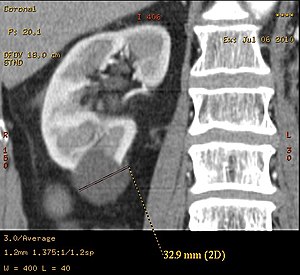

Diagnosis includes imaging with ultrasound, CT and/or MRI. The least expensive, non-invasive, and most reliable method is ultrasonography but smaller cysts may escape detection, while the resolution of CT and MRI will enable smaller cysts to be captured. However, the increased complexity and expense of CT and MRI is usually reserved for higher risk situations. MRI can be used to monitor the development of cysts and growth of kidneys.[citation needed]Genetic test can be applicable to those who have a family history of PKD but is expensive and fails to detect PKD in 15% of cases where it is present.[citation needed]